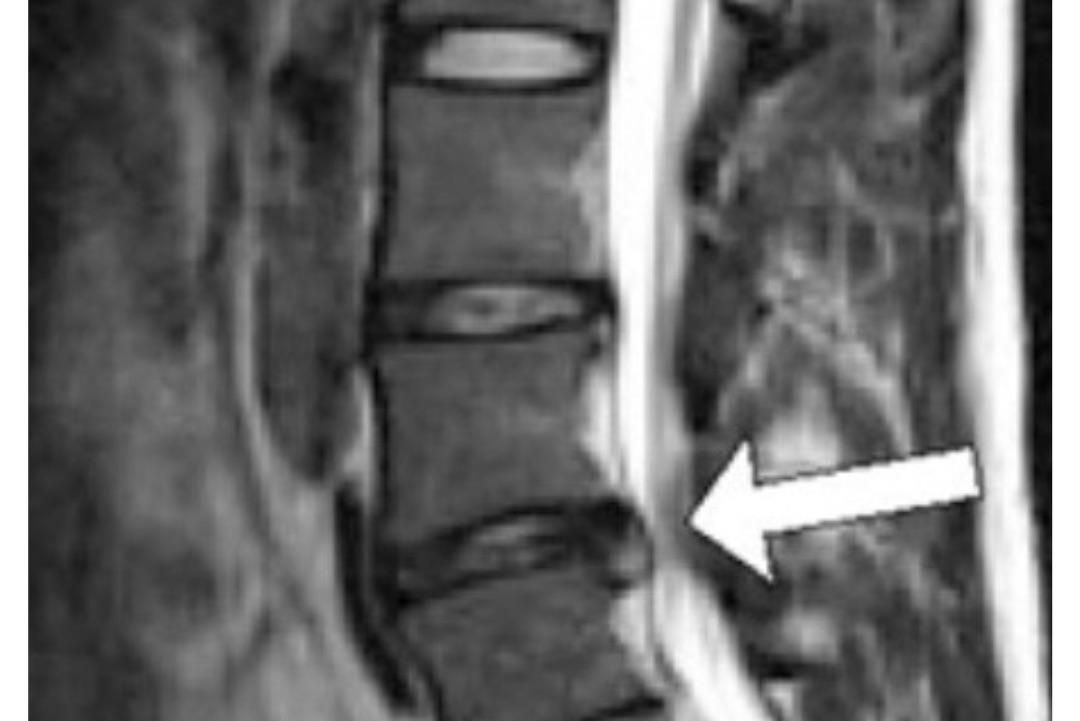

椎間板ヘルニアで歩くのも

痺れがありましたが

歩けるようになりました!

A3ヶ月ほど前から突然右足が痺れるようになり、歩くと痺れが強くなる状態でした。通勤で駐車場から会社までの2、3分の距離を歩くのもつらくてこのまま良くならないのではないかと不安でした。

A整形外科を受診し「椎間板ヘルニア」と診断され痛み止めの薬を処方してもらいました。ブロック注射も何回が打ちましたが根本的に痺れが改善されることはありませんでした。

A右足の痺れが良くなり歩くのも苦でなくなりました。普段は自宅で教わったセルフケアを続け、定期的にメンテナンスをお願いしています。